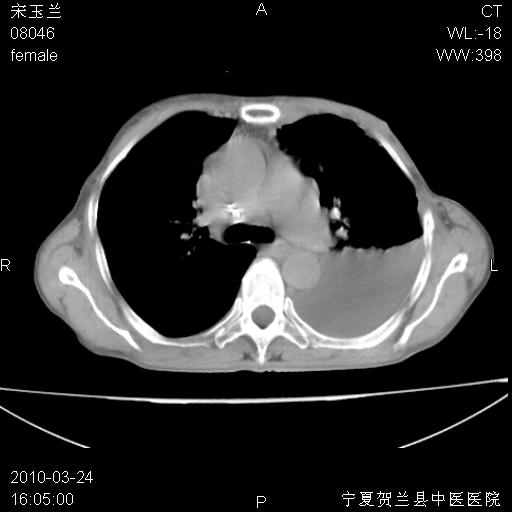

以下是引用zxl51642在2010-3-24 18:49:00的发言:[br]结合乳腺癌术后病史,考虑双肺及纵隔淋巴结多发转移、左侧胸膜转移并左侧大量胸水、左下肺膨胀不全。